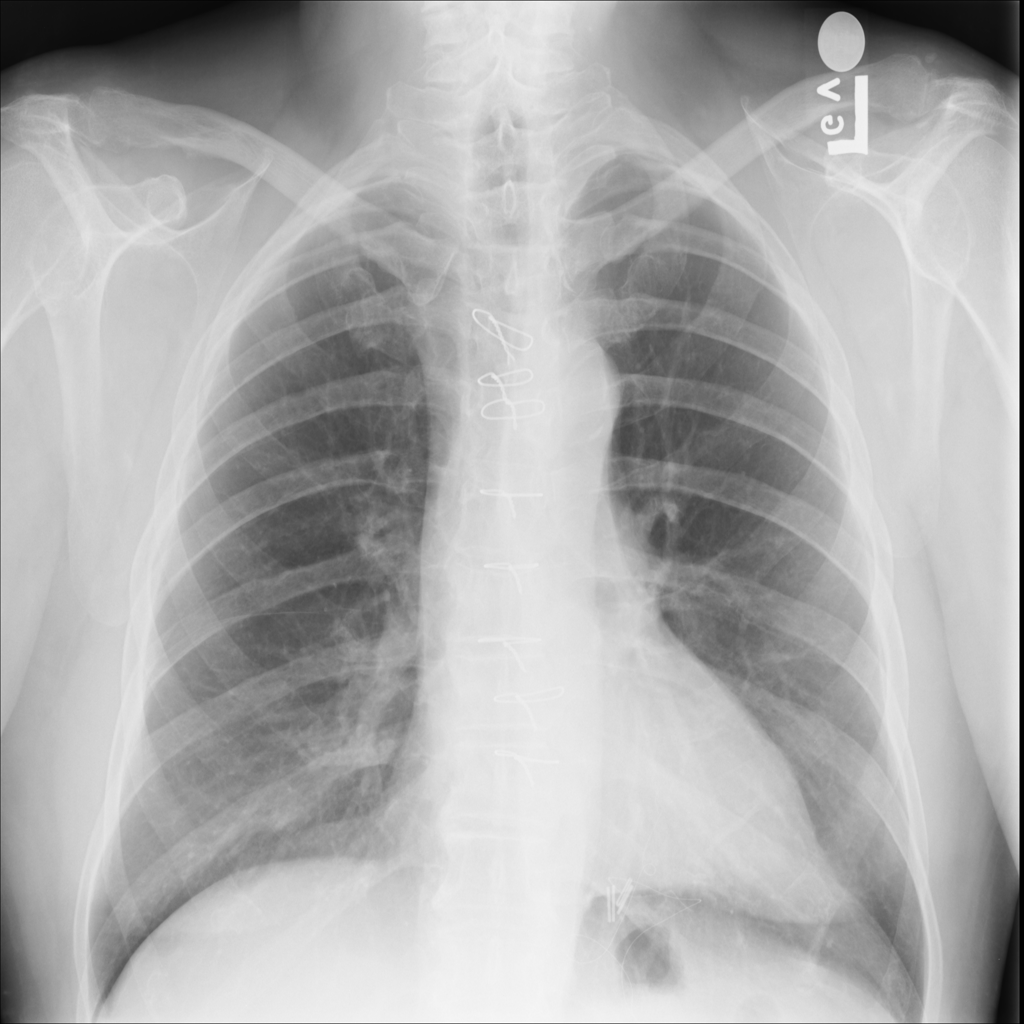

PAT-B0DB · IMG-003Emphysema

PAT-B0DB · IMG-003

PA